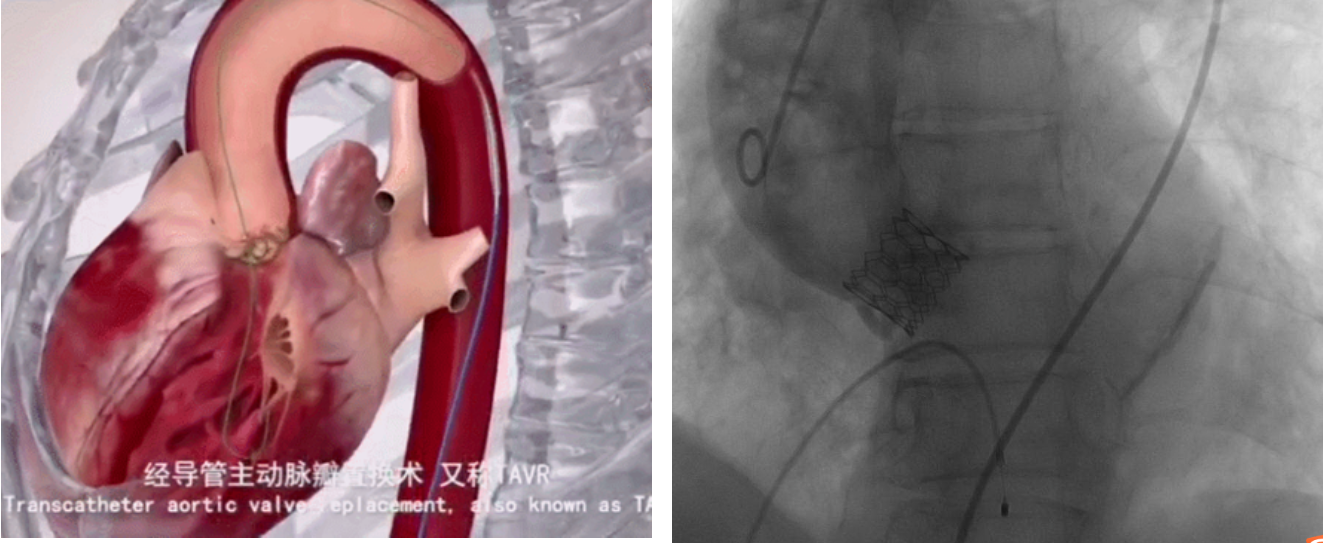

TAVI是将人工生物瓣膜通过介入导管输送到心脏主动脉瓣区打开,完成人工瓣膜的植入,恢复瓣膜功能的一种技术,具有创伤小、术后恢复快等优点。

如下图所示,取得了极其满意的效果。

瓣膜释放 瓣膜释放后造影